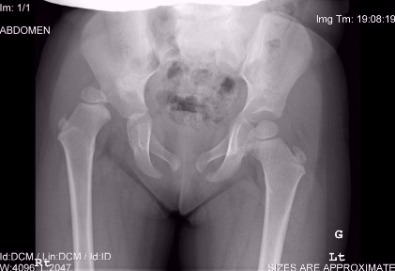

Πέντε χρονών κορίτσι με εγεφαλική παράλυση πριν από χειρουργική επέμβαση. Οι ακτινογραφίες έδειξαν υπεξάρθρημα ισχίου.

Προεγχειρητικές ακτινογραφίες κοριτσιού ηλικίας τρεισήμιση ετών στην Κύπρο, που παρουσιάστηκε με χολώτητα λόγω συγγενούς εξάρθρωσης του δεξιού ισχίου